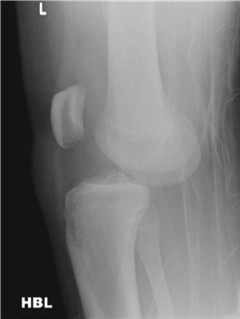

What does this radiograph tell you and what are your immediate concerns about the patient?

This lateral radiograph shows a dislocation of the left knee. This is usually a high-energy injury so I would be concerned about general patient status and other injuries. As far as this injury is concerned I would be most worried about a popliteal artery injury, which occurs in around 25 % of patients with this injury.

How do you carry out an initial assessment of this patient?

I would assess and document the neurovascular status of the limb before reducing this dislocation, under sedation, as an emergency. After reduction I would again perform a careful neurovascular examination. If there is any suggestion of vascular injury, exploration or angiography is indicated. A โ€˜normalโ€™ pulse may not exclude injury; an ankleโ€“brachial pressure index of less than 0.9 is abnormal.

How do you classify these injuries?

T hese injuries are classifi ed according to the direction of dislocation of the tibia in relation to the femur. Anterior dislocations are most common followed by posterior, lateral, medial, and rotatory dislocations. Up to 20% of knee dislocations have spontaneously relocated and do not, therefore, fi t into this classifi cation.

An alternative way of classifying is by description of the ligamentous damage incurred.

This patient has an arterial injuryโ€” how will you proceed?

I would arrange for this patient to go urgently to a theatre where a plastic or vascular surgeon will be available. Prompt reconstruction takes priority and would normally involve an interpositional vein graft. The knee would be stabilized, and thus the repair protected, by placing a spanning external fi xator. Lower limb fasciotomies are also performed to avoid a reperfusion compartment syndrome.

Which nerve is most commonly damaged and how would you manage this?

The common peroneal nerve is the most frequently involved, occurring in around 20โ€“30 % of cases. I would treat this expectantly, although a large proportion will not fully recover.

How do you provide defi nitive treatment for an unstable knee?

I would obtain an MRI scan to characterize ligamentous structures that have been damaged. Associated fractures must also be sought. Additional information may be found by performing an EUA. Repair and/or reconstruction of ligamentous structures should be performed by somebody with experience in this area.

Treatment choices lie between early reconstruction of the postero-lateral corner (PLC) and posterior cruciate ligament (PCL), with delayed anterior cruciate ligament (ACL) reconstruction, and early bracing/rehabilitation with late reconstruction.